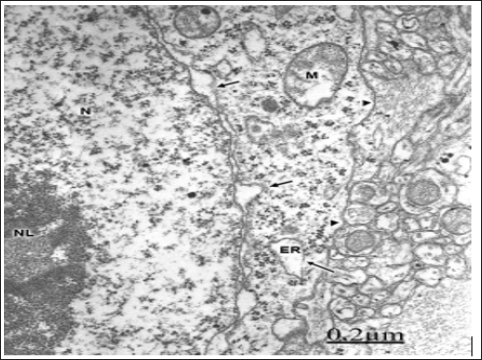

In vascular anomaly, the perifocal cerebral cortex exhibits a microstructure like that observed in normal animal brain cortex. The plasma membrane of non-pyramidal neurons shows in moderate oedema atly normal and continuous structure. The plasma membrane form endocytic and clathrin coated vesicles internalizing toward the cytoplasm. The limiting plasma membrane of rough endoplasmic reticulum cisterns exhibit fragmented areas and detachment of membrane associated ribosomes. The nuclear envelope appears irregularly dilated (Figures 1 & 2). Disaggregation of ribosomes was earlier demonstrated by Dux in primary cortical and hippocampal neuronal cultures after brief histotoxic hypoxia.

Figure 1: Anomaly of anterior cerebral artery. Right pa-rietal cortex. Non-pyramidal nerve cell showing an irreg-ularly dilated nuclear envelope (short arrows), enlarged endoplasmic reticulum cisterns (ER), detachment of mem-brane associated ribosomes (long arrows), and a contin-uous limiting plasma membrane (arrowheads). Note the prominent nucleus (N), the nucleolus (NL), the swollen mitochondria (M), and the non-dilated extracellular space in the neighboring neuropil that features moderate brain edema.